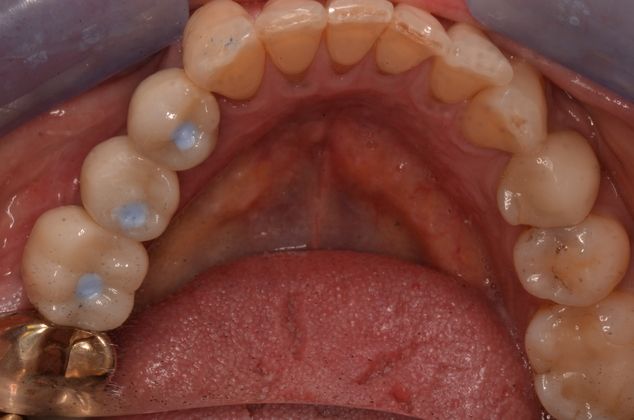

Three missing lower teeth replaced with implants and screw retained crowns.